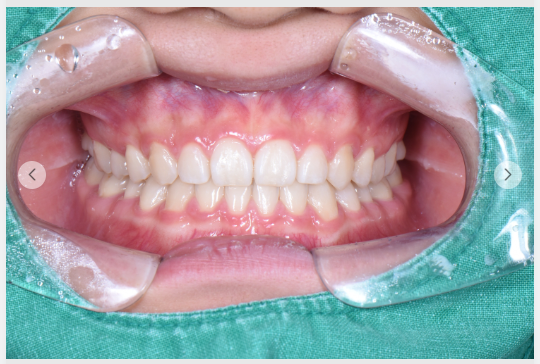

(부정교합 교정 치료 전(위)/후(아래))